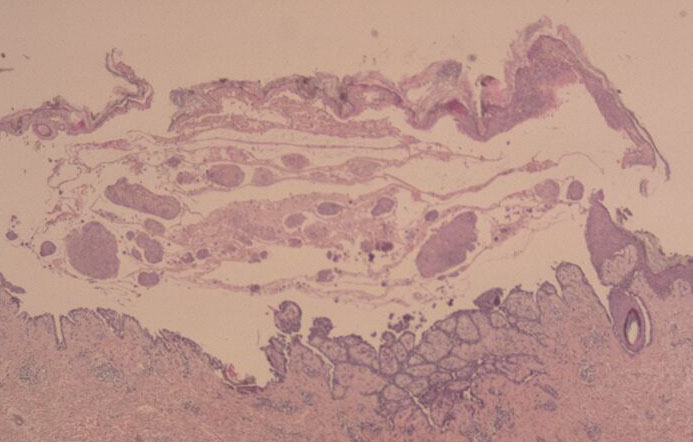

The earliest recognized change may be either eosinophilic spongiosis rarely or, more commonly, “spongiosis” in the lower epidermis . This spongiosis may actually represent the earliest manifestation of acantholysis rather than true spongiosis as defined earlier. Acantholysis leads first to the formation of clefts and then to blisters in a predominantly suprabasallocation . The intraepithelial acantholysis may extend into adnexal structures or occasionally be higher in the stratum spinosum. The basal keratinocytes, although separated from one another through the loss of attachment, remain firmly attached to the dermis like a “row of tombstones.” Within the blister cavity, the acantholytic keratinocytes, singularly or in clusters, have rounded condensed cytoplasm about an enlarged nucleus with peripherally palisaded chromatin and enlarged nucleoli. In some patients, there are varying quantities of antidesmoglein 1 and antidesmoglein 3 antibodies, leading to variable planes of acantholysis. There is little inflammation in the early phase of blister formation. If present, it is usually a sparse, lymphocytic perivascular infiltrate accompanied by dermal edema. However, if eosinophilic spongiosis is apparent, numerous eosinophils may infiltrate the dermis. The phenomenon of eosinophilic spongiosis occurs occasionally in other blistering diseases, particularly in their early phases, including acute contact dermatitis, pemphigus foliaceus, bullous pemphigoid, herpes gestation is, drug eruptions, spongiotic arthropod bite reactions, and transient acantholytic dermatosis. Several important changes ensue as the lesions age. First, a mixed inflammatory cell reaction consisting of neutrophils, lymphocytes, macrophages, and eosinophils may develop. Because of the instability of the blister roof, erosion and ulceration may occur. Older blisters may also have several layers of keratinocytes at the blister base because of keratinocyte migration and proliferation. Last, there may be considerable downward growth of epidermal strands, giving rise to so-called villi (Fig. 9-9D). The evaluation of patients with only oral lesions is difficult, because intact blisters are rarely encountered due to the trauma of mastication, and biopsies may show only erosion and ulceration. Indeed, it is best to sample the edge of a denuded area with intact mucosa in an attempt to demonstrate the typical pathologic changes. Clinicians frequently cannot distinguish between an ulcer and the intact mucosa, as both are often white and shaggy. In patients with only oral lesions, biopsies of intact oral mucosa for DIF testing are more sensitive than biopsies of lesions for routine light microscopic evaluation. Therefore, biopsy from the normal maxillary and upper buccal mucosa is necessary when there is extensive ulceration. Cytologic examination using a Tzanck preparation is useful for the rapid demonstration of acantholytic epidermal keratinocytes in the blisters of pemphigus vulgaris. For this